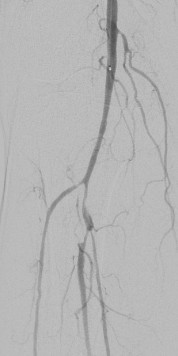

術(shù)中DSA:箭頭提示雙髂動(dòng)脈血栓栓塞,血流中斷

術(shù)中DSA:雙髂動(dòng)脈血流恢復(fù)